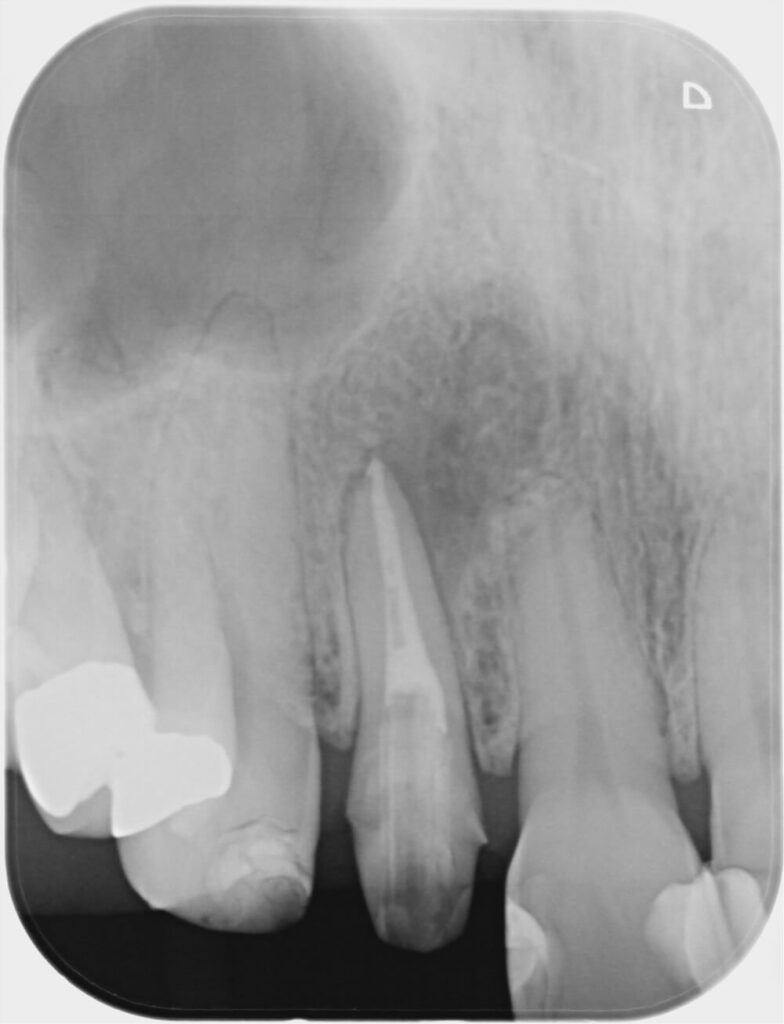

■術前→ 1年6か月後の変化

初診時(左) 1年6か月後(右)

2年後の再評価では、

- 痛みなし

- 腫れなし

- 日常生活でも快適に機能

- レントゲン上で骨の改善確認

と、とても良好な状態でした。